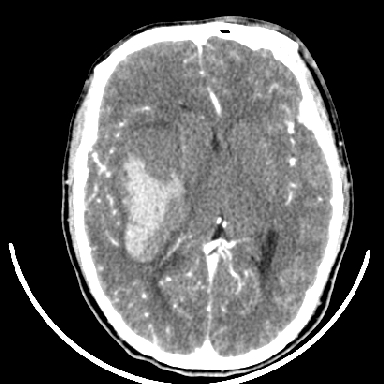

标题: CT6056:脑出血(血管畸形?) [打印本页]

标题: CT6056:脑出血(血管畸形?)

m 40突发头痛左侧偏瘫3小时

考虑高血压性脑出血,依据:

1是高血压性脑出血的好发部位,形态呈肾形,是高血压性脑出血的常见形状

2增强时占位效应加重了,考虑出血还没有停止

3病灶周围水肿不是太厉害,一般肿瘤出血水肿多非常明显

4病灶周围的‘软组织’影没有明显的强化

5至于脑血管畸形引起的出血,暂时没有看到明显的畸形血管影,也不太支持

支持右侧基底节脑出血

右侧基底节区脑出血.

支持右侧基底节区(主要为外囊区)原发性脑出血。

另附部分资料:“血液溢出血管外形成血肿,其内含有大量血红蛋白、血浆白蛋白,球蛋白,因这些蛋白对x线的吸收系数高于脑质,故ct呈现高密度阴影,ct值达40~90h,最初高密度灶呈非均匀一致性,中心密度更高,新鲜出血灶边缘不清。基底节区血肿多为“肾”型,内侧凹陷,外侧膨隆,因外侧裂阻力较小,故向外凸,其它部位血肿多呈尖圆形或不规则形”

术中抽出40ml陈旧血液,血肿底部似见一条索血管影